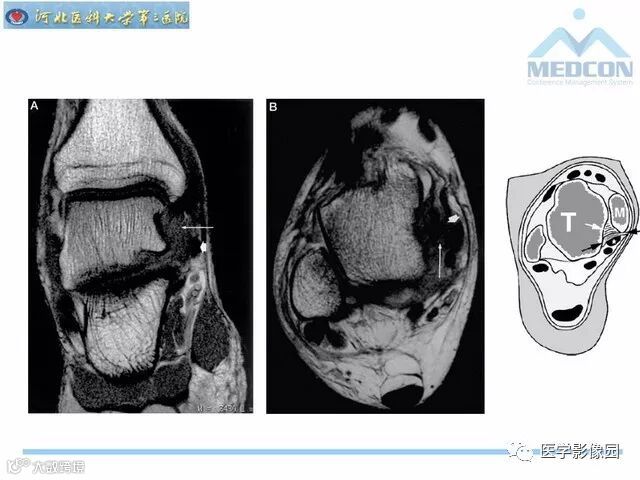

踝关节撞击综合征影像诊断,干货满满,值得收藏!

导读:踝关节撞击综合征影像诊断。干货满满,值得收藏!

踝关节撞击综合征影像诊断。干货满满,值得收藏!